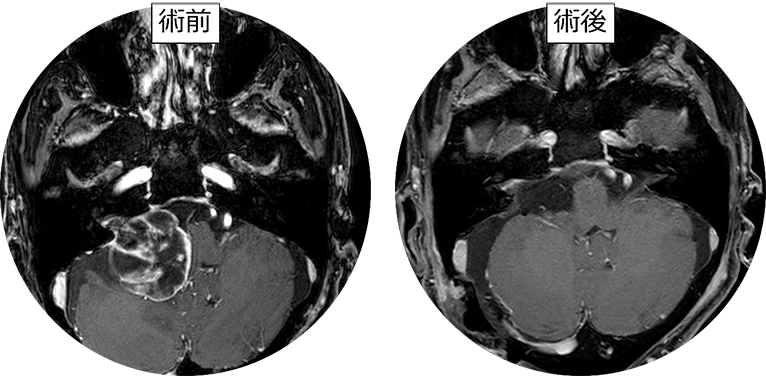

「聴神経腫瘍・小脳橋角部腫瘍の手術とマネージメント」定価: ¥ 19800裁断済みです。#本